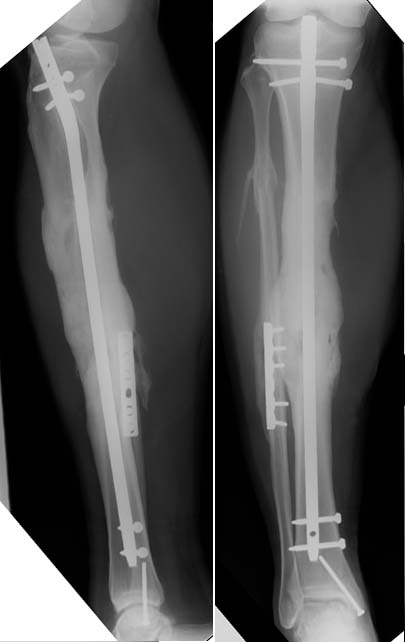

Here's an example of a 30s yo male patient with a similar (but "tibial only") open segmental defect after a motorcycle accident, treated with nailing, several I&Ds, defect beads, closure/coverage, then a single allo-auto(combo)grafting @ 7 weeks after injury.

We anticipated union problems so we used a small diameter hollow nail, and left it available for easy exchange...but never needed to.

These films were taken 8 months after injury. You can see where the defect was. But, he did have fibular support.

Maybe he's just real lucky.